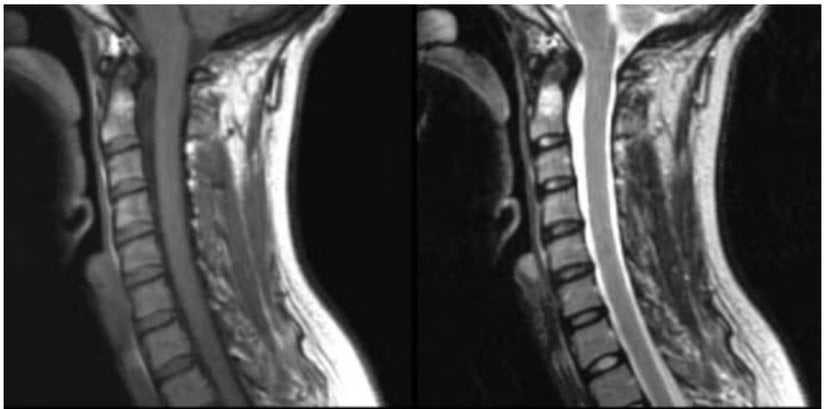

MR cihazlarında X-ışınlarının aksine güçlü manyetik alanlar ve radyo dalgaları kullanılarak kemiklerin ardındaki yumuşak dokular, beynin karmaşık yapısı, eklemlerdeki en küçük yırtılmalar dahi yüksek detayla ortaya çıkarılır. Cihazın çalışma prensibi ise atom çekirdeklerinin dinamiği ve kuantum fiziği ile ilgilidir.

- Uzunlamasına Gevşeme: Burada protonlar emdikleri enerjiyi ısı şeklinde çevrelerindeki atomlara ve yağ, su, protein moleküllerine aktarırlar. M⃗\vec{M} vektörünün düşey bileşeni olan Mz⃗\vec{M_z}'nin orjinal büyüklüğünün %63'üne düşmesi için geçen süre T1 zamanı olarak adlandırılır. Yağ, su, kas ve patolojik dokuların T1 zamanları farklıdır. Bu farklılık, T1 ağırlıklı görüntülerdeki doku ayırt edilebilirliğinin yani kontrastın ana kaynağıdır.

- Enine Gevşeme: Protonların kendi aralarındaki küçük manyetik alan farklılıkları presesyon hızlarında ve fazlarında değişikliklere yol açar. Bu da yatay düzlemdeki senkronize hareketin bozulmasına ve yatay düzlemdeki manyetizasyon vektörü bileşeni olan Mxy⃗\vec{M_{xy}}'nin sönmesine neden olur. Diğer bir deyişle RF darbesi sonrası oluşan Mxy⃗\vec{M_{xy}} zamanla azalarak sıfıra döner. Burada tanımlanması gerekn T2 zamanı Mxy⃗\vec{M_{xy}} vektörünün orijinal büyüklüğünün %37'sine düşmesi için geçen süredir. Farklı dokuların T2 zamanları da farklıdır.